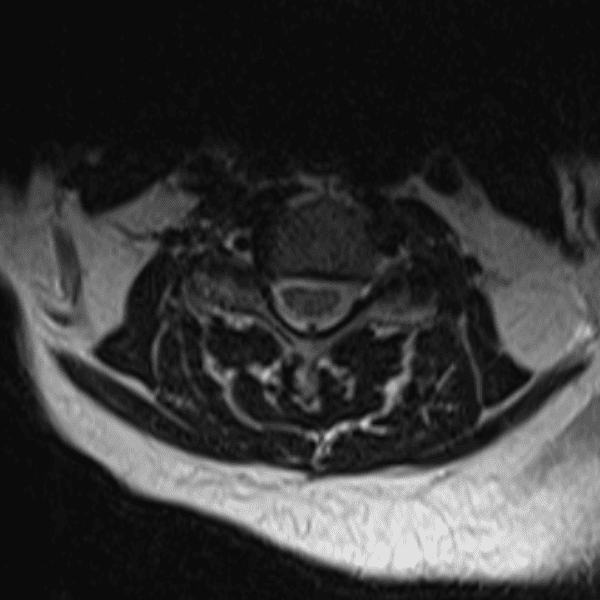

Simulates call by including subtle or difficult cases and some normals.

35 cases